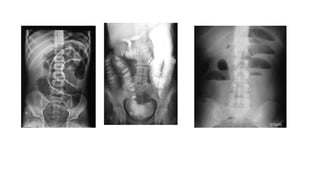

- Exámenes de imagen son

los estudios Rx de tórax,

abdomen Ultrasonografía

Invaginación intestinal

Es la primera causa de abdomen agudo y oclusión intestinal en los lactantes, 80% de

los casos ocurre en menores de 2 años

Más de 90% de los casos la invaginación es ileocólica, pero puede ocurrir en cualquier

segmento del intestino

Estudios de Imagen